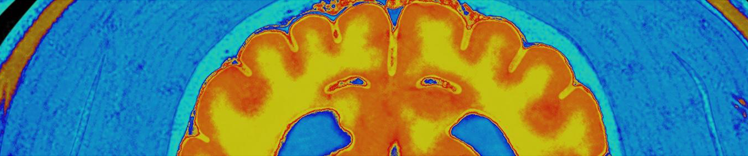

RESONANCIA MAGNÉTICA

Cambios en el cerebro que envejece

Los cambios físicos en el cerebro asociados con el envejecimiento incluyen:

- Atrofia (contracción) tisular en algunas regiones

- Volumen ventricular aumentado

- Pérdida de neuronas y sinapsis y reducción de la formación de nuevas neuronas

- Acumulación de proteínas anormales